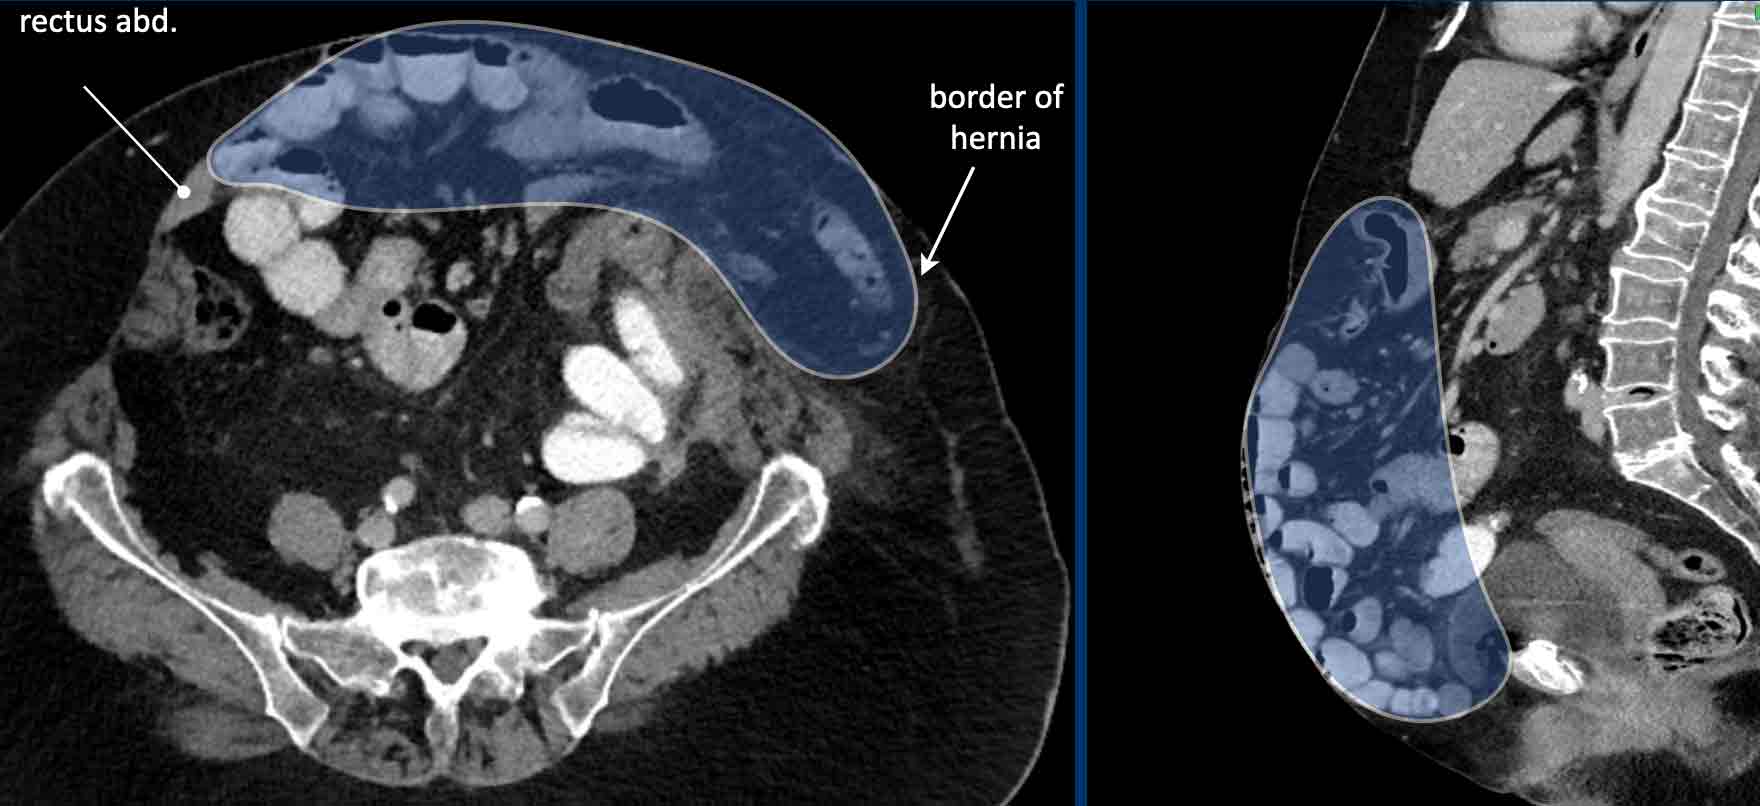

Lumbar hernia. (a) Axial computed tomography (CT) demonstrating Lumbar Hernia Radiology Assistant They are distinguished primarily based on type, location and content. We present the ct findings of seven lumbar hernias: Disc herniation is defined as a focal displacement of disc material ( < 25% of the disc circumference) beyond the limits of the. Examples of abdominal wall hernias: Abdominal hernias/herniae may be congenital or acquired and come with varying eponyms. Disc. Lumbar Hernia Radiology Assistant.